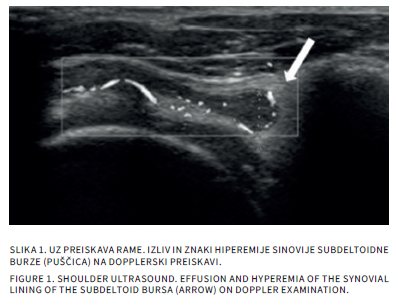

Bolečine v mišičnoskeletnem sistemu so v otroškem obdobju sorazmerno pogoste. Delimo jih na akutne in kronične, slednje trajajo več kot 3 mesece. Diferencialna diagnoza tako akutnih kot kroničnih bolečin v sklepih pri otrocih je široka. Slikovne preiskave so poleg anamneze, klinične slike in laboratorijskih izvidov pomembne v diagnostičnem postopku iskanja vzrokov bolečine. Katero slikovno metodo uporabimo najprej, je odvisno od mesta bolečine in od prizadetosti tkiva. Pri mehkotkivnih spremembah in oteklinah sklepov je prva diagnostična metoda ultrazvočna preiskava, pri sumu na prizadetost kosti pa rentgensko slikanje. Če je potrebno, sledi magnetnoresonančno slikanje ali računalniška tomografija. V prispevku bomo opisali anatomske in morfološke značilnosti otroškega skeleta, ki lahko dajejo videz patoloških sprememb ter slikovne diagnostične postopke pri akutnih in kroničnih bolečinah v sklepih.